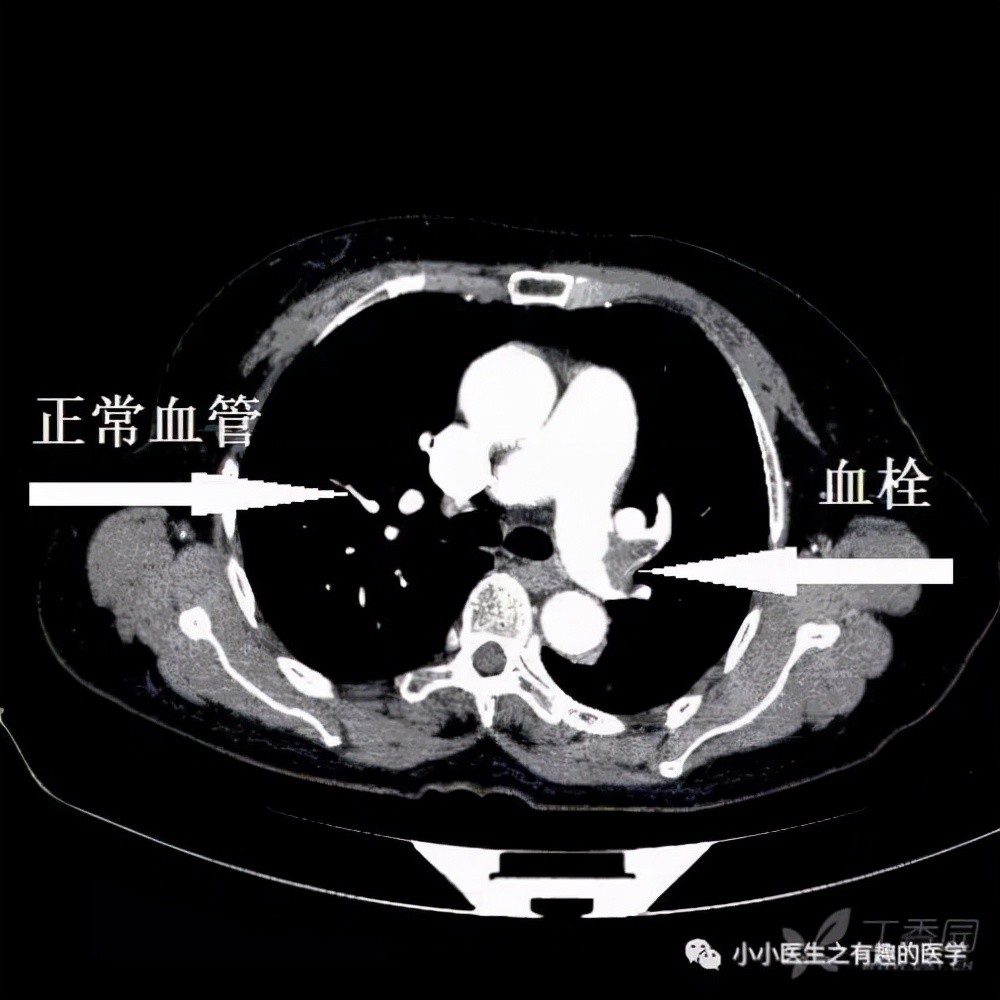

比如小徐有胸闷的症状,同时心电图S1Q3T3这是典型的肺栓塞心电图,以及血氧偏低才83%,正常成人血氧饱和度应该在95%以上;加之后来D-二聚体、动脉血气、肺部增强CT这些都能帮助诊断肺栓塞。